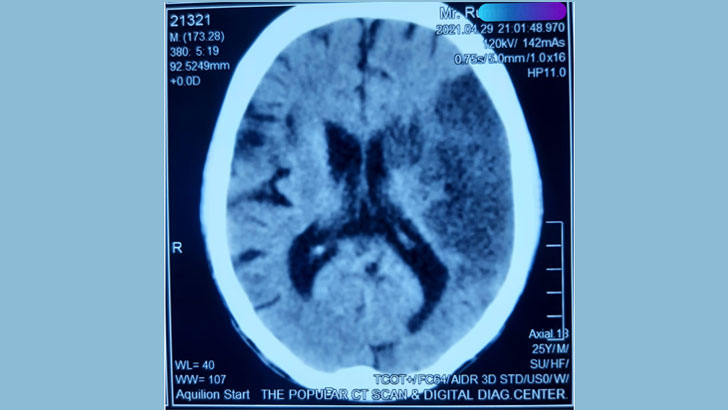

সেই রোগীর সিটিস্ক্যানের ছবি

সিটি স্ক্যানের ফিল্মে আমার চোখ আটকে রইল। আমার থিসিসের সাবজেক্ট ছিল স্ট্রোক পরবর্তী মানসিক সমস্যা। আমার এই ইন্টারেস্টিং গবেষণা আমি ইউরোপ, আমেরিকা, জাপান, নিউজিল্যান্ড সহ বিশ্বের বেশ কিছু দেশের সায়েন্টিফিক সেমিনারে প্রেজেন্ট করি।

আরমানের সমস্যাটাও তাই। স্ট্রোকের পর মানসিক সমস্যা। সেই রাতে আরমানের ব্রেইনের গুরুত্বপূর্ণ একটি রক্তনালীর রক্ত চলাচল (LMCA-Left Middle Cerebral Artery block) বন্ধ হয়ে বিশাল বড়ো সড়ো একটা স্ট্রোক হয়েছে। এ রকম বয়সে স্ট্রোক ব্যতিক্রম আর এই প্রেজেন্টেশন অতি বিরল।